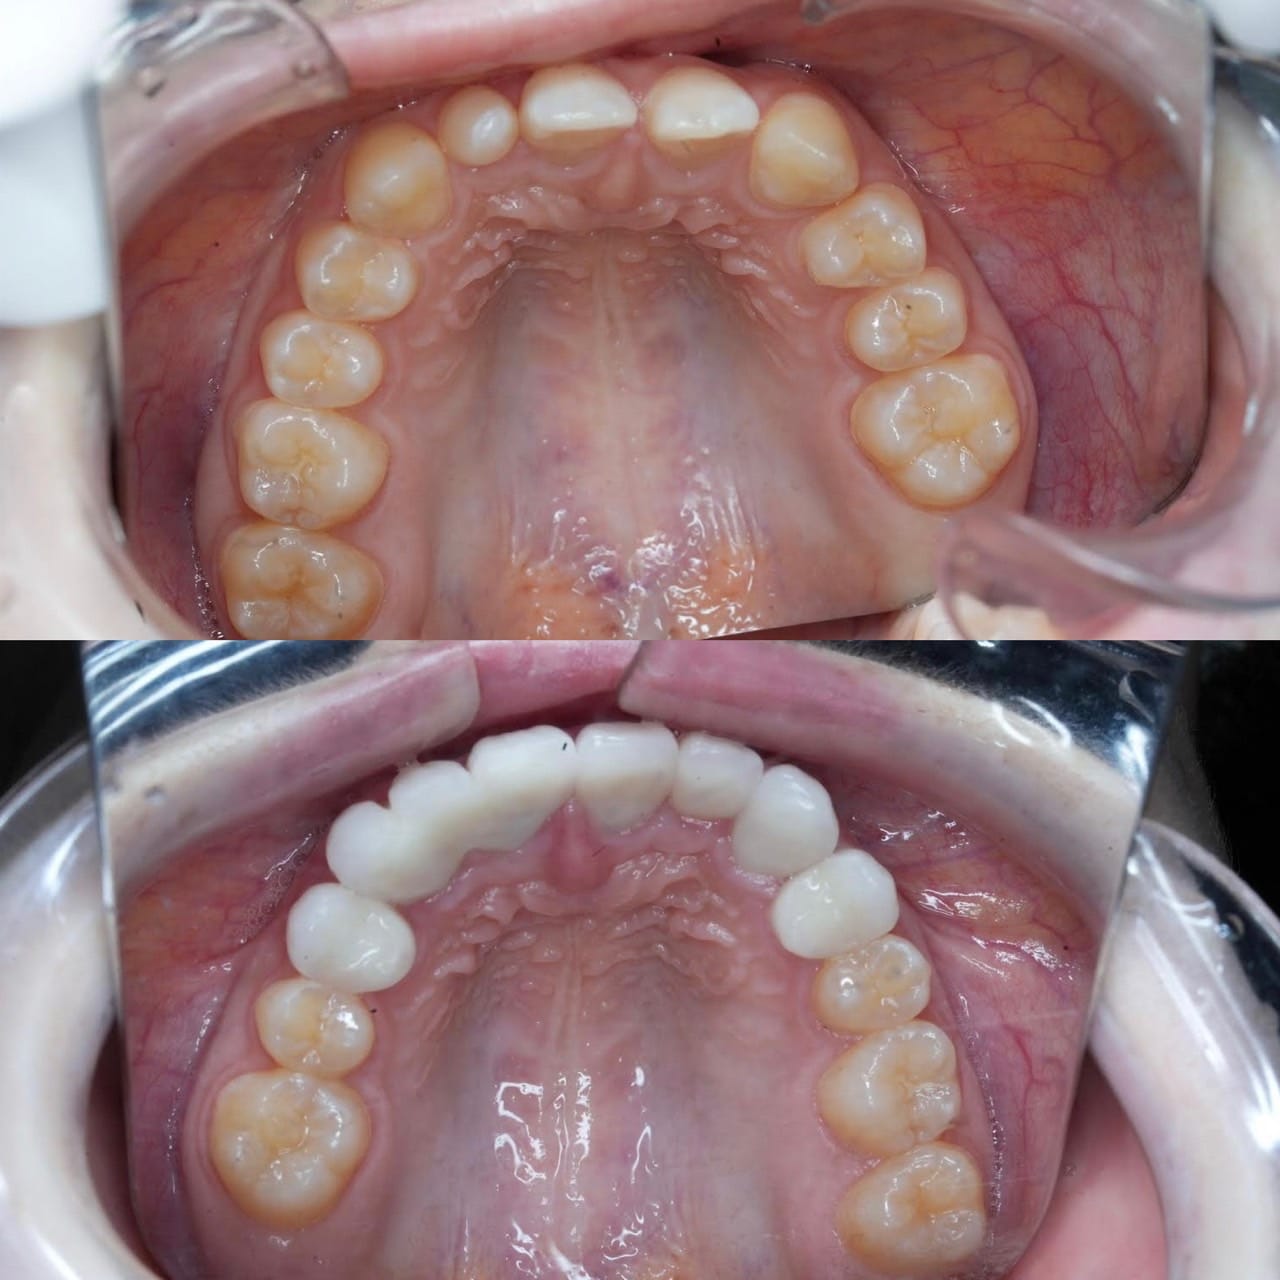

Case032

メジャーリーグでも活躍した元プロ野球選手の山口俊さんのセラミック治療を担当いたしました。

「他院で治療を受けたセラミックが欠けた」というのが主訴でしたが、よく診察するとセラミック欠けただけではなく、被せ物がしっかりと合っていないことが原因で歯茎の腫れがあり、歯石や汚れもつきやすい状態でした。また、歯列も若干歪んでいたので、この機会に全て治療いたしました。

治療後は透明感のある白さで、綺麗な歯並びになりました。また、セラミックをきちんと綺麗に削って適合よくセットしたことにより、歯茎の腫れも改善しました。

セラミックを入れた所の歯茎が腫れていて悩まれてる方はぜひご相談ください。

綺麗に削って適合よくセラミックをしてあげれば必ず改善します。